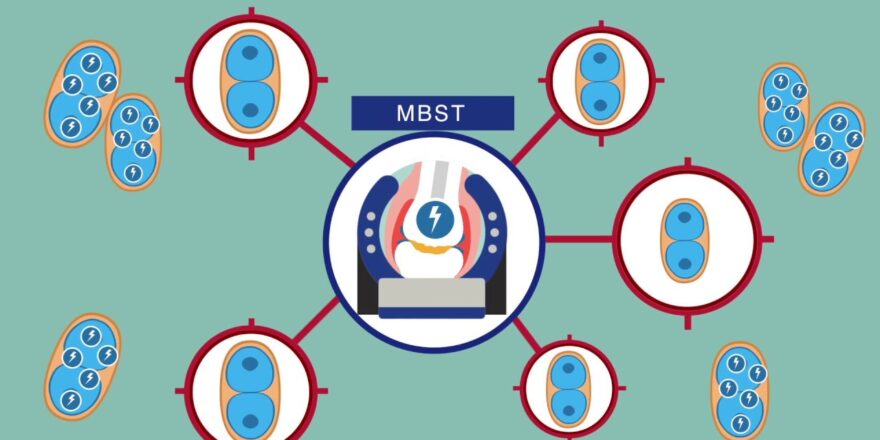

Understanding MBST Therapy for Joint Recovery

Molecular Biophysical Stimulation Therapy (MBST) is transforming the landscape of pain management and tissue regeneration, particularly in joint ...